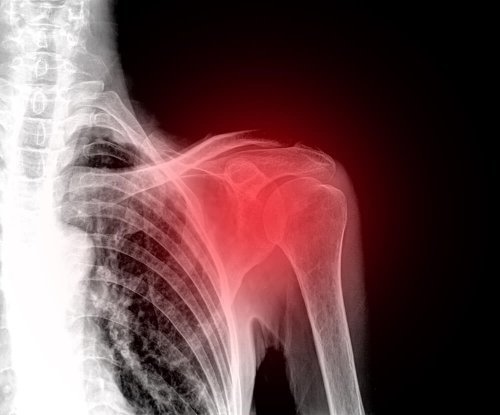

A ruptura do manguito rotador é uma patologia que afeta o ombro com muita frequência em pessoas de meia idade. É uma das principais causas de dor no ombro na atualidade.

Os sintomas ocorrem dependendo da gravidade da lesão. Mesmo assim, o sintoma predominante é a dor no ombro. Da mesma forma, todos os movimentos dessa articulação são limitados.

Primeiro, para diagnosticar a ruptura do manguito rotador, o médico fará um exame físico. Durante este, examinará a capacidade de movimento, a força, e a dor que ocorre na articulação.

Por outro lado, geralmente são utilizados testes complementares, como ultrassom ou ressonância magnética. A ultrassonografia permite avaliar os tendões e músculos enquanto ocorre o movimento. Além disso, é um exame acessível e não invasivo.